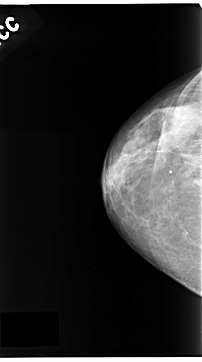

C_0123_1.LEFT_CC

LEFT_CC LINES 4688 PIXELS_PER_LINE 2544 BITS_PER_PIXEL 12 RESOLUTION 50 OVERLAY

FILE: C_0123_1.LEFT_CC.OVERLAY

TOTAL_ABNORMALITIES 1

ABNORMALITY 1

LESION_TYPE MASS SHAPE IRREGULAR MARGINS ILL_DEFINED

ASSESSMENT 5

SUBTLETY 5

PATHOLOGY MALIGNANT

TOTAL_OUTLINES 1

BOUNDARY